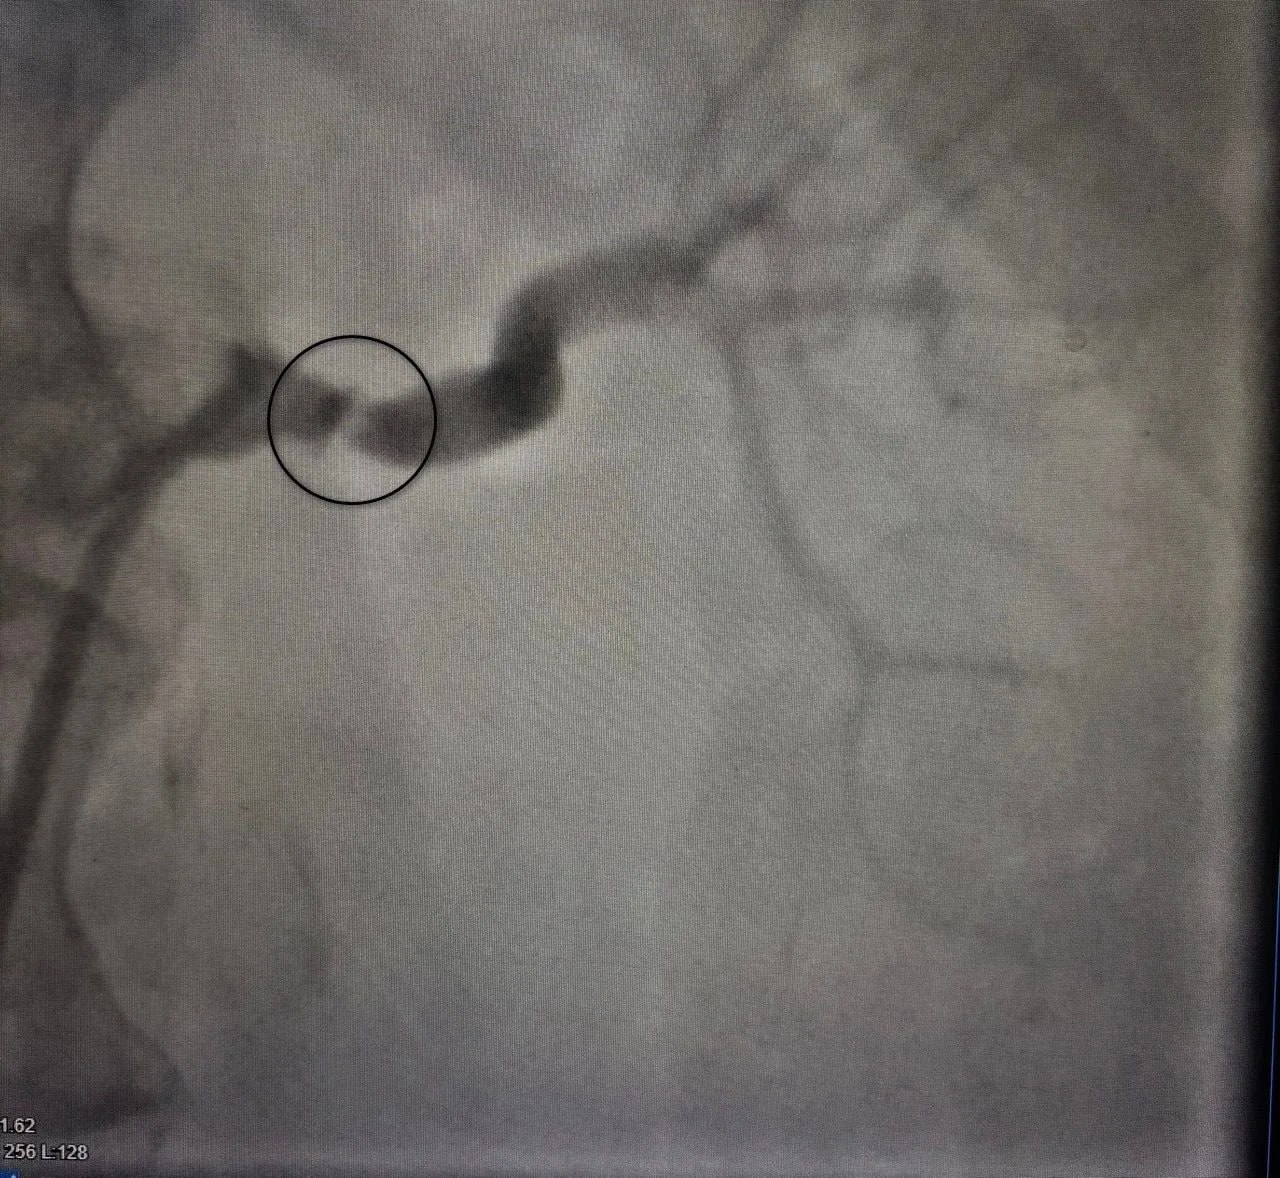

У 57-летней женщины была сужена левая почечная артерия, что привело к тяжелой, невосприимчивой к многокомпонентной медикаментозной терапии артериальной гипертензии. У женщины также было ожирение и сахарный диабет второго типа. Цифры артериального давления достигали критических значений – 240 мм ртутного столба, что представляло серьезную угрозу для жизни.

Пациентке провели диагностику, а затем «расширили» артерию и установили стент. Операция привела к кардинальному улучшению состояния пациентки. Артериальное давление стабилизировалось, что позволило значительно сократить медикаментозную нагрузку.